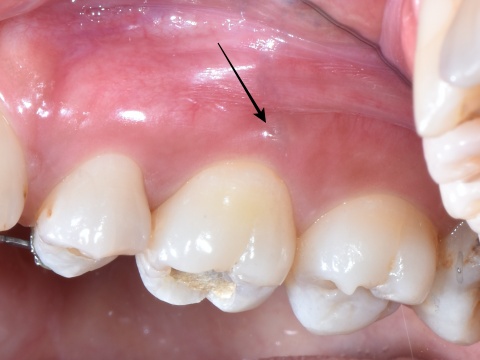

言葉で書くのは簡単ですが、これには非常に時間がかかりとても困難な治療でした。そこにMTAセメントを用い、根の先端の方(赤矢印)と吸収部(黄色矢印)を同時に埋めました。

黄色矢印の左の方を見ていただくとわかると思いますが、外にはみ出しているのがわかるかと思います。

これはMTAセメントを押し込んで、わざとはみ出しています。

この後歯茎を開いて、はみ出したMTAセメントと除去しきれていない外部吸収部を除去して、グラスアイオノマーというセメントにより同部を埋めました(赤矢印)。

これも言葉にして書くと簡単なのですが、これをピッタリ埋めるのが非常に難しかったです。